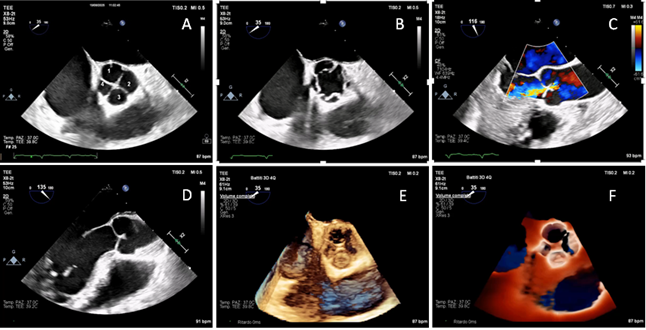

Transoesophageal examination was performed using a X8-2t (Philips, Amsterdam, The Netherlands) probe. Midesophageal aortic valve short-axis view (35° angle) demonstrated four cusps, with two equal-sized larger cusps and two unequal-sized smaller cusps, which means Hurwitz & Roberts type F quadricuspid valve (QAV) (A) [1,2]. Midesophageal aortic valve short-axis view in mid-systole showed the four commissures (B). Color Doppler midesophageal long-axis view demonstrated central moderate aortic regurgitation (vena contracta width = 4 mm, no holodiastolic flow reversal in proximal descending aorta) (C). Midesophageal long-axis view (135° angle) highlighted the characteristic leaflet coaptation pattern of QAV, with a coaptation length of 6 mm measured in end-diastole (D). Three-dimensional high resolution four-beats (61 Hz) standard reconstruction (E) and three-dimensional TrueVue (Philips, NL) rendering (F) provided a detailed visualization of cusps configuration supporting the diagnosis of QAV and its classification (Video S1). QAV is a rare congenital abnormality with a prevalence of less than 0.05% in the general population [3,4]. Hurwitz and Roberts QAV classification is the most widely adopted one, and it identifies seven morphologic variants, from type A to type G [1,2]. This condition is frequently associated with progressive valve dysfunction, primarily due to isolated aortic regurgitation, while significant aortic stenosis is quite rare. The cumulative incidence of aortic valve intervention in QAV is comparable to that observed in bicuspid aortic valve. However, cumulative incidence of aortic surgery in patients with QAV is lower compared to those with bicuspid aortic valve, although it is higher than in the general population [2,5]. Aortic valve replacement with either a mechanical or a biological prosthesis can be performed. However, aortic valve repair should be considered as a first-line option, particularly in young patients with suitable anatomy, even though long-term durability data in this setting remain limited; tricuspidization of a QAV may be an option, particularly in cases with two larger and two smaller leaflets (Hurwitz and Roberts types F and G), or in the case of three larger and one smaller leaflets (Hurwitz and Roberts types B). In the literature, two cases of type F QAV associated with severe aortic regurgitation have been reported, without other significant valvular or aortic lesions. Both patients underwent aortic valve replacement [6,7]. If aortic dilatation is detected, Bentall or Ross procedures should be considered [8,9]. Anatomical studies of normal tricuspid aortic valves reported a mean coaptation length of 3.8 ± 0.8 mm [10]; however, corresponding data on QAVs are currently lacking. QAVs may show a greater coaptation length, potentially related to valve morphology, and future studies on this topic are needed.